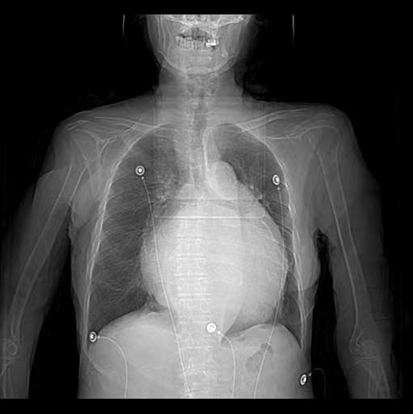

图一:患者胸片显示心影显著增大,以左心房增大为主

患者因“发作性气短20余年”之主诉入院,多次心脏超声诊断为风湿性心脏瓣膜病二尖瓣狭窄,此次因症状再发加重入院。经评估患者二尖瓣瓣口面积为0.67cm2,二尖瓣跨瓣压差为22mmHg,左房前后径94mm,左右径109mm,为重度风湿性二尖瓣狭窄伴罕见巨大左心房。在心内二科主任寿锡凌带领下,全科室充分讨论。因患者年龄大、基础情况差、无法耐受外科手术治疗,药物治疗不能解除瓣膜狭窄,只能选择经皮二尖瓣球囊扩张成形术。但鉴于患者巨大左心房已使心脏结构发生了巨大变化,单纯通过传统DSA影像结合经胸心脏超声指引下穿刺房间隔引起心脏破裂、心脏填塞、房间隔穿刺部位不佳影响手术操作、二尖瓣狭窄严重难以寻找二尖瓣瓣口、球囊扩张时球囊扩张位置不佳、术中难以即刻评估瓣膜扩张效果等均会导致手术失败进而威胁患者生命。考虑到心腔内超声宛如“心腔内的眼睛”可实时为术者提供心腔内的解剖结构毗邻关系,弥补传统DSA影像结合经胸心脏超声的不足,能为术者决策实时提供指导,确保手术能够安全、准确、顺利完成,最终决定为患者行心腔内超声指引下经皮二尖瓣球囊扩张成形手术。